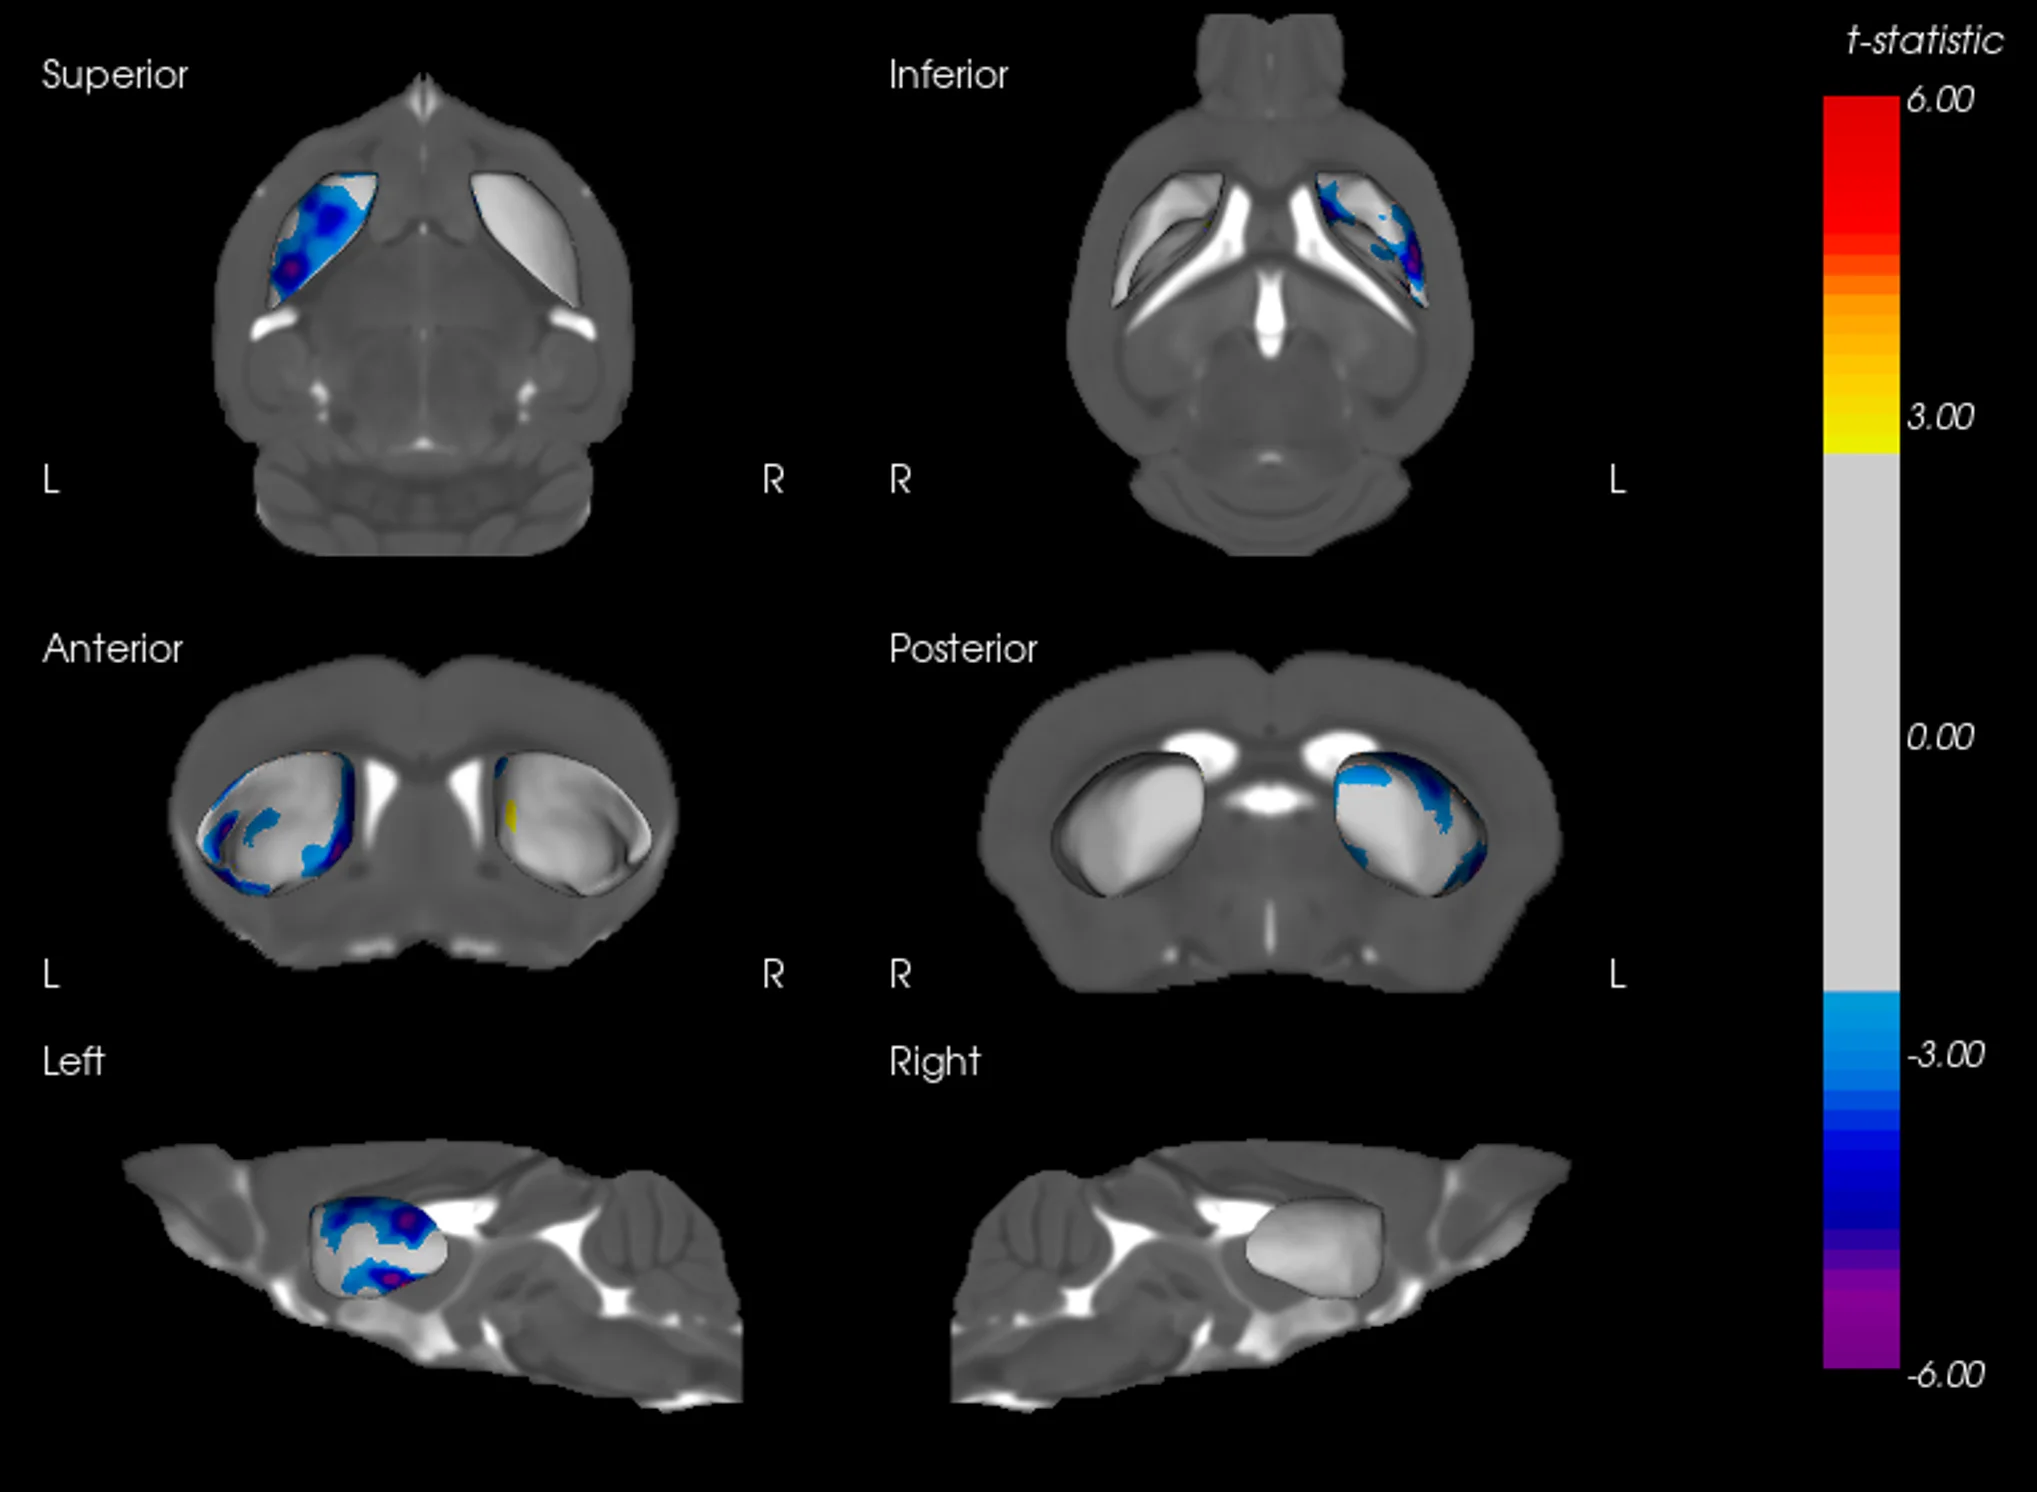

AAV-Tau 小鼠纹状体表面变形

纹状体的三维表面渲染图,显示 AAV-Tau 注射小鼠左半球向内变形的局部区域。冷色表示与向内位移相对应的具有统计学意义的负t统计量。变形仅限于同侧,与 tau 诱导的萎缩一致。

纹状体变形与 TH 密度之间的相关性

纹状体表面变形图与相应的 TH 密度相关性的叠加。暖色区域代表具有显著正 t 统计量的区域,表明局部表面变形与 TH 标记密度之间存在密切关系。这些区域突显了 AAV-Tau 小鼠的多巴胺能神经支配区。